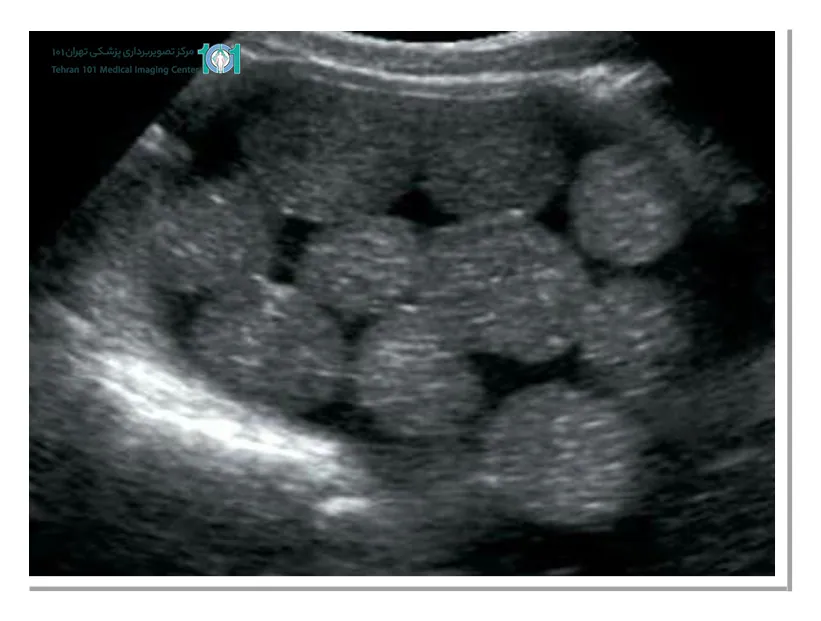

پولیپ رحمی چیست؟

پولیپ رحمی (Endometrial polyps) یکی از تودههای اکوژنی شناخته میشود که دلیل تشکیل آنها رشد بیش از حد سلولهای پوششی (اندومتر) رحم است که به دیواره آن چسبیدهاند. اندازه این تودهها متفاوت بوده و اغلب خوش خیم هستند.

البته گاها پیش میآید که بدخیم یا دچار تغییرات بدخیمی شوند. تودههای رحمی به واسطه یک پایه نسبتا پهن یا باریک به سطح درونی رحم میچسبند. پولیپهای رحمی هنگام باروری بعد از باروری و به طور کلی در تمام سنین قابل مشاهده است.

علائم پولیپ (توده اکوژنی) رحم

- خونریزی مداوم با شدت متغییر

- خونریزی در فاصله بین دو پریود

- نازایی

- خونریزی ناگهانی

- خونریزی حتی بعد از یائسگی

درمان پولیپ رحمی

در اغلب موارد پولیپهای رحمی کوچک به راحتی و خودبهخود از بین میروند و نیازی به درمان ندارند. در باقی موارد حتما باید تشخیص داده شود که نوع و اندازه اکوژنهای رحمی چقدر است تا درمان متناسب با آنها صورت گیرد.

در موارد حادتر پزشک ضایعات رحمی را به وسیله مخصوص به آرامی جدا میکند تا علائم آن برطرف شوند. برای تشخیص اکوژنهای رحمی میتوانید به مرکز تصویربرداری پزشکی تهران مراجعه کنید تا از تشخیص دقیق برخوردار و در صورت لزوم به مراحل درمان بپردازید.